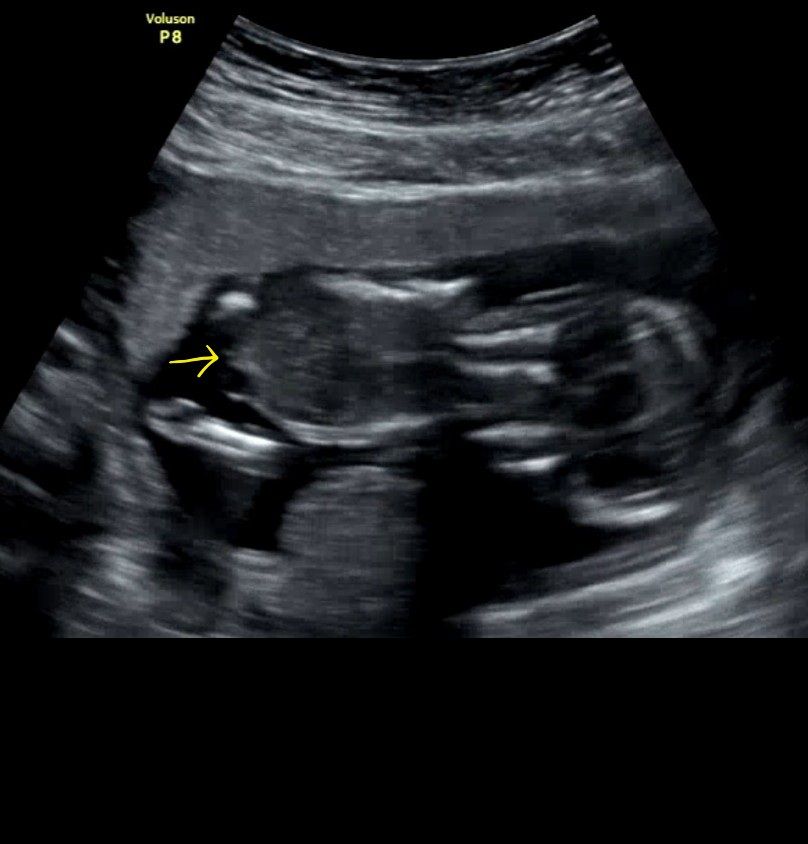

둘째성별이 너무 궁금해서 빌리 ai 각도법 계속하는데 딸이래요 근데 제눈에는 뭔가보이는거같기도한데 계속 딸이래요 사진은 둘째정면인데 다리사이에 보이는거같기도하거든요...뭐로보이나요..? 그래서 첫째 초음파사진찾아서 ai 해봤는데 첫째도 딸이래요 참고로 저희첫째는 아들입니다:)